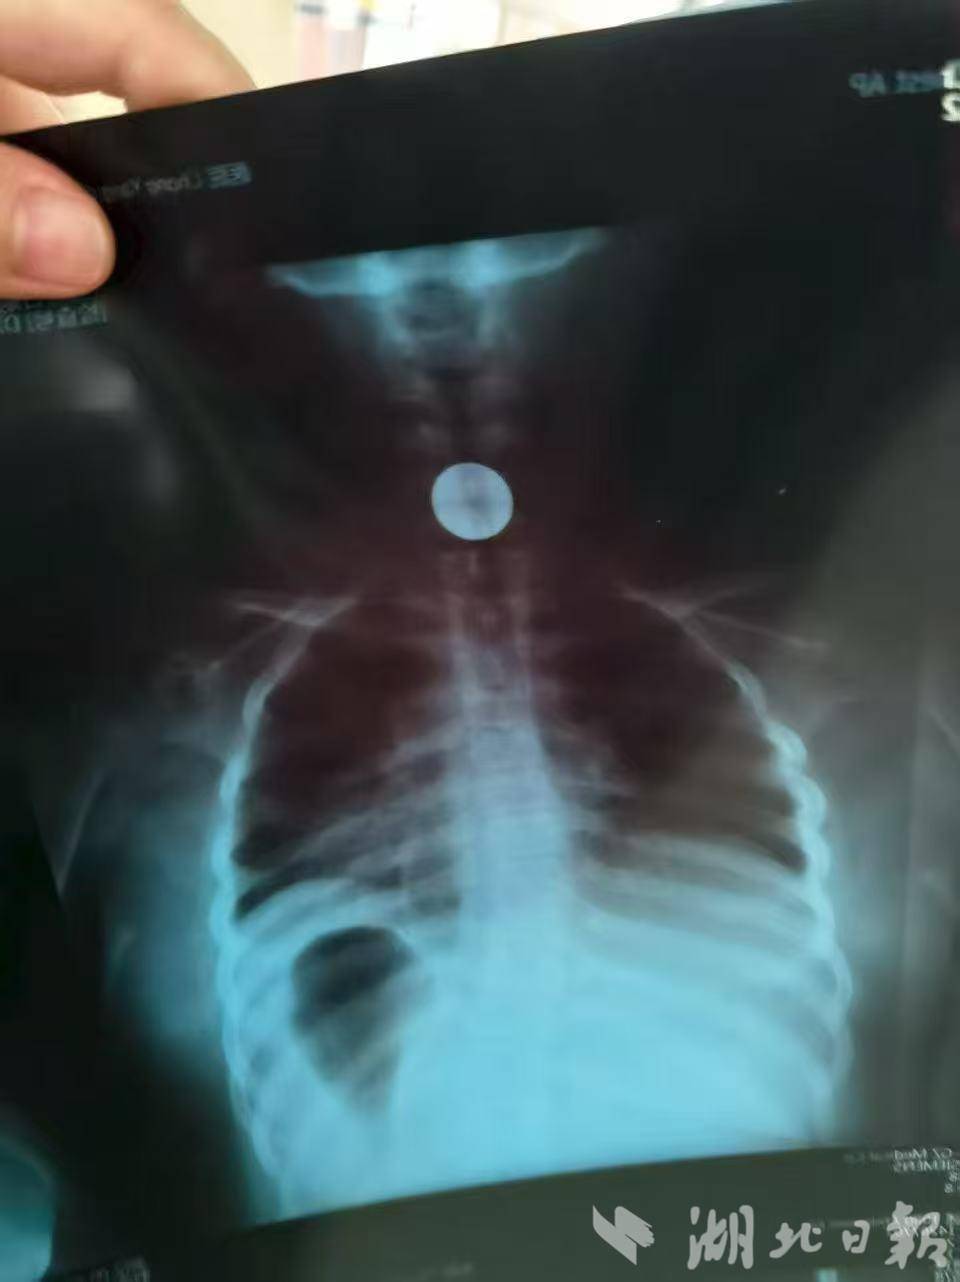

科室主任袁启阳问明情况后,让家长将女孩紧急抱至诊室,经胸片检查,硬币嵌顿在食管上段。由于硬币直径远大于儿童食管宽度,长时间滞留极易导致黏膜水肿、出血、穿孔,甚至窒息,随时可能危及生命。